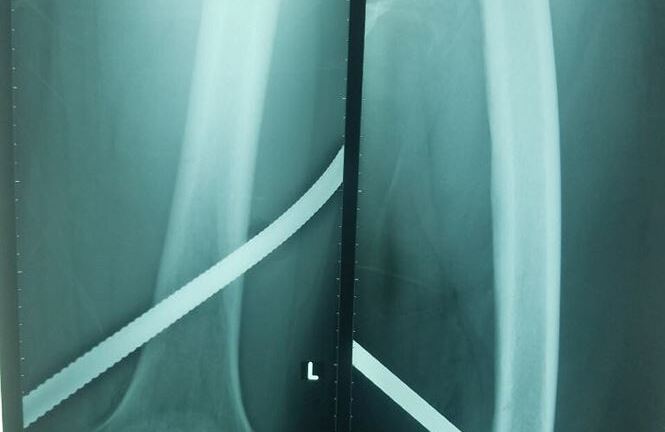

Dị vật được các bác sĩ phẫu thuật lấy ra từ cột sống của bệnh nhân - Ảnh: TTXVN. |

Bệnh nhân nhập viện trong tình trạng tê bì tầng sinh môn, bí đái và có vết thương ở thắt lưng bên trái. Các bác sĩ đã tiến hành phẫu thuật làm sạch đường vào và lấy hoàn toàn dị vật cho bệnh nhân.

Tiến sĩ Nguyễn Hoàng Long đánh giá, với tình huống của bệnh N.C.H, đó là vết thương ít gặp ở ống sống, bởi lực tác động vào tương đối đặc biệt, cắm thẳng vào tủy sống, thay vì tổn thương thường gặp khác. Nếu không điều trị kịp thời, tổn thương tủy sống có thể khiến người bệnh gặp phải những di chứng rất nặng nề.